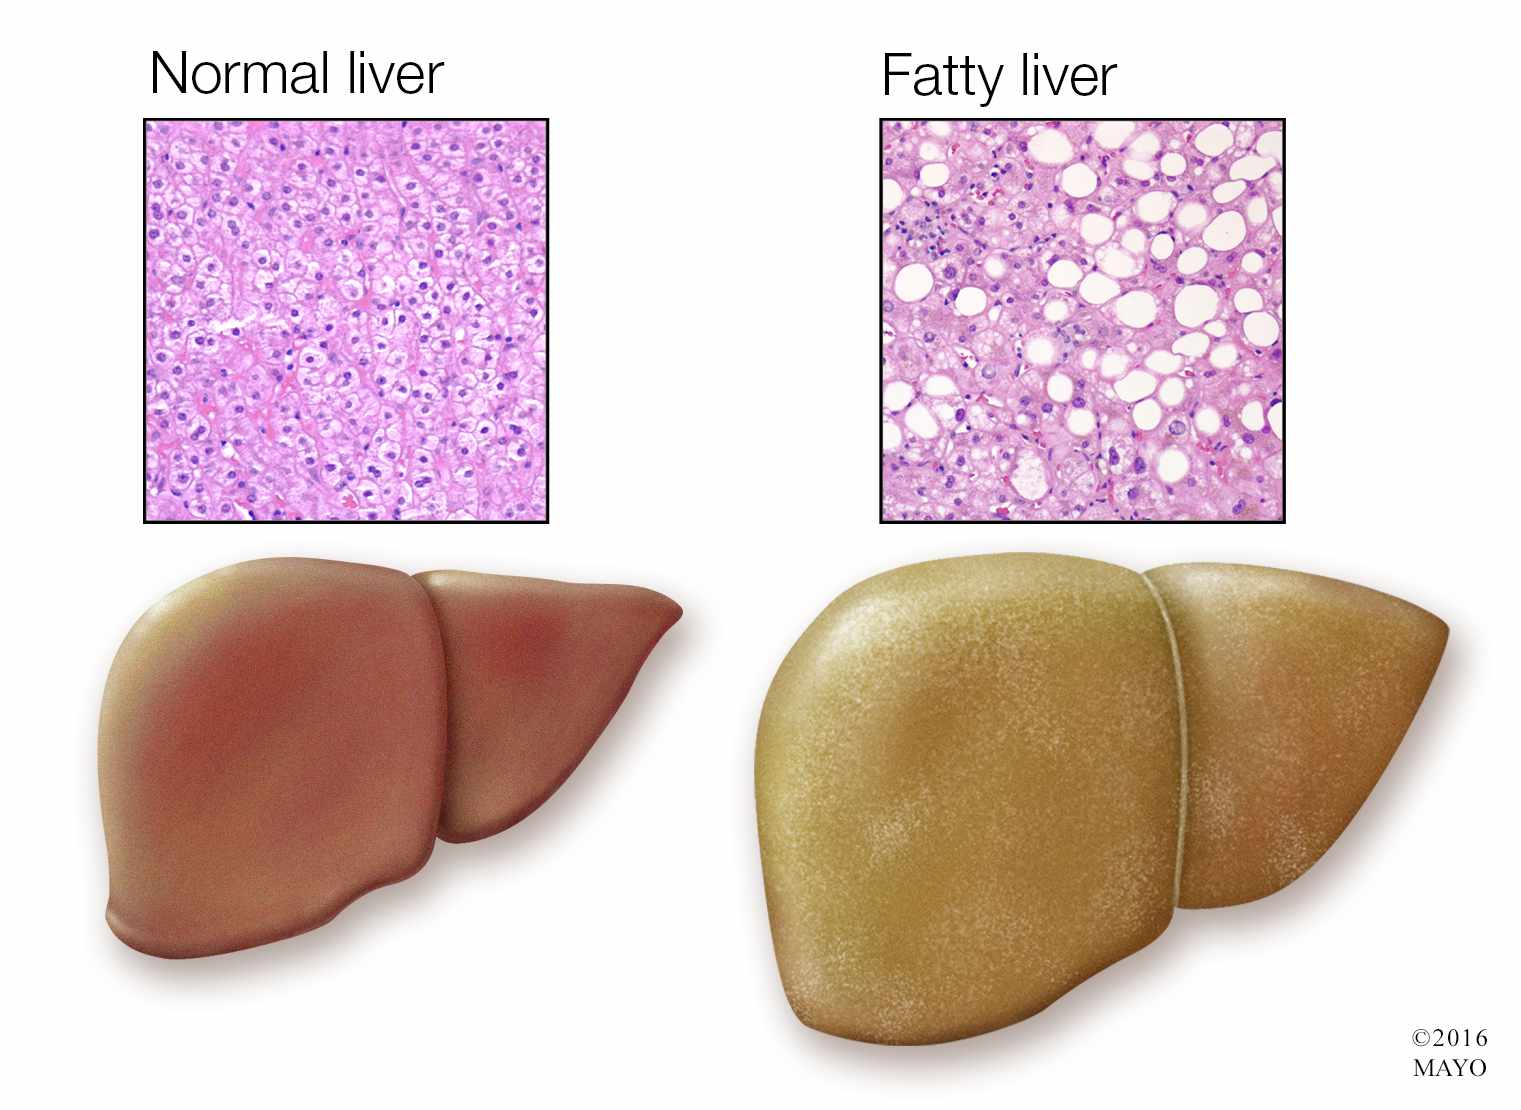

Изображения заболеваний печени: признаки и симптомы